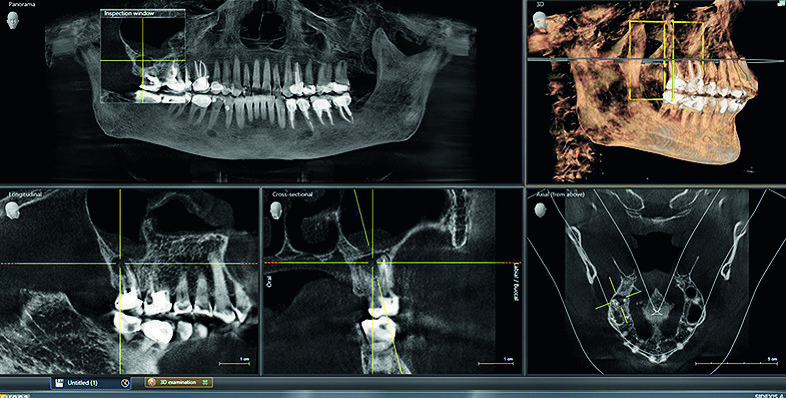

Il paziente presentava segni dentari e sintomi di apnea del sonno, tra cui una forma ad arco stretto, una lingua smerlata, serraggio e vie aeree strette. La visualizzazione della scansione Orthophos SL 3D in SICAT Air ha aiutato il paziente a comprendere meglio il collegamento tra le vie aeree superiori e l’odontoiatria. Il passo successivo è stato uno studio sul sonno a casa che, in effetti, ha rivelato un’apnea notturna moderata.

Per il piano di trattamento, abbiamo utilizzato dati di imaging 3D per creare l’oral appliance SICAT OPTISLEEP. Il flusso di lavoro completamente digitale è efficiente e l’oral appliance può essere ordinato direttamente attraverso il software SICAT Air, con il risultato finale di avere un paziente felice e soddisfatto (Figg. 1-4). Questo è stato un caso particolarmente gratificante perché, dopo aver indossato l’apparecchio, la paziente ha constatato di aver avuto una notte di sonno riposante come non capitava da tanto tempo, ricordandosi come ci si sente a svegliarsi ben riposati.

Fig. 2_Esame 3D con Sidexis 4.